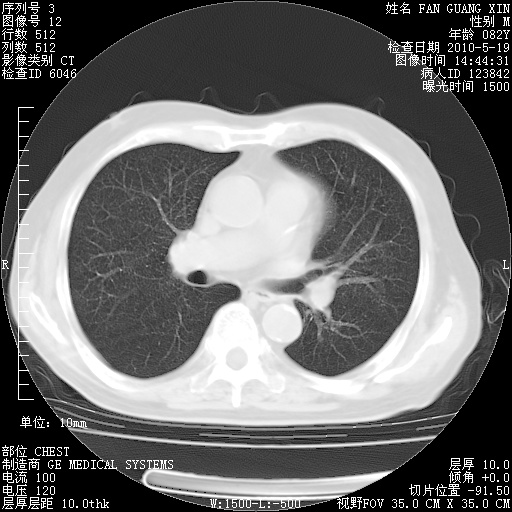

复查肺部CT,明显好转。为什么发热呢?

治疗3周后的肺部CT

治疗3周后的肺部CT纵隔窗